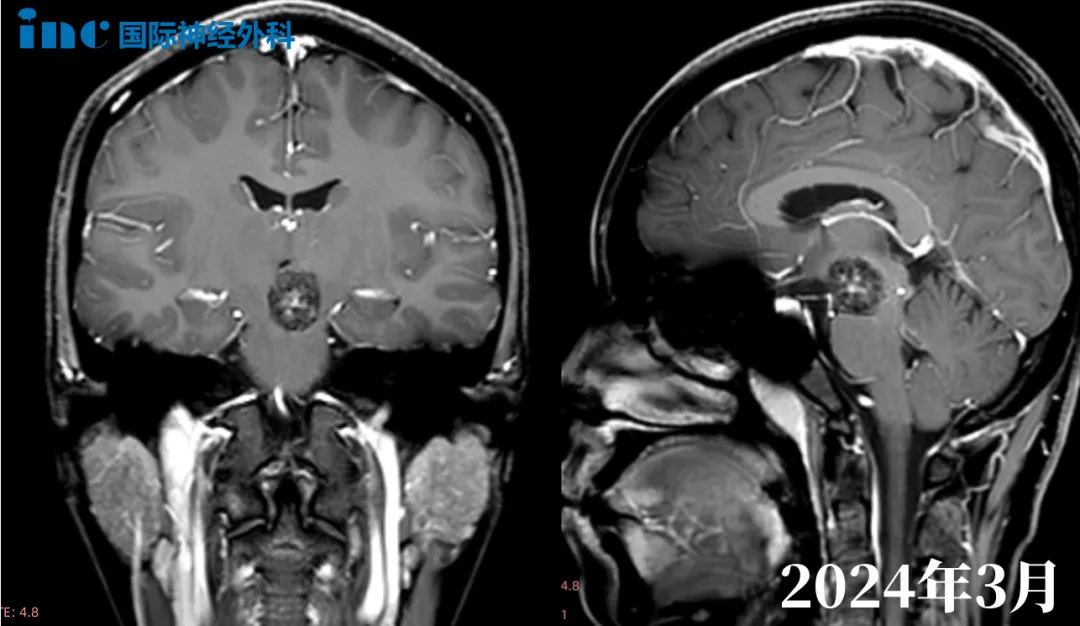

北京时间2024年3月27日,“国际脑干教授”,国际神经外科联合会(WFNS)教育与技术委员会前主席巴特朗菲教授匆匆走出苏州大学附属儿童医院手术室。这是一名年仅7岁的脑干海绵状血管瘤患儿,脑干出血病情危急。通过医院、铁路部门等多方联动,患儿千里迢迢被转运到苏州手术,终于抢救成功。而巴教授作为这台手术的主刀,携苏州大学附属儿童医院神经外科团队为生命中枢“排雷”,帮助果果重获了新生。

小林一开始出血时症状较轻,然而2024年春节前夕,再次出血。右侧胳膊出现明显麻木,腿部无力,无法行走。对症治疗后可以走路了,但是麻木还是很明显。学习成绩优异的他,对于自己要求较高,同时也急切希望找到更好的治疗途径。当得知巴教授即将来华的消息,春节前一两天,小林和母亲立刻咨询巴教授。巴教授也在春节期间迅速回复。再次远程视频后,更加坚定了手术的决心。

“想问一下教授除了手术还有其他的方案吗?”,手里拿着整理好的资料和问题,顾先生担负着妻子的期望来到巴教授咨询室。2019年,30岁出头的妻子由于左腿麻木及幻听症状检查发现岛叶占位。随后行肿瘤切除手术,术后病理结果显示:右侧颞叶弥漫性胶质瘤(星形细胞瘤WHOⅡ级)。2023年5月,常规随访CT检查显示肿瘤增大。2024年1月妻子开始频繁出现癫痫症状,核磁影像显示肿瘤进展或复发。

巴教授认真查看了核磁影像后表示,目前肿瘤已经有了明确的手术指征,虽然肿瘤呈弥漫生长,但是这个位置自己能够达到85%到90%的切除率。首先由于肿瘤已经涉及岛叶、颞叶、额叶,体大。其次一开始术后病理为二级,需要手术明确目前肿瘤是否恶化。对于他们关心的除了手术的其他方案外,对于胶质瘤的治疗,标准就是较大水平手术切除后再进行后续辅助放化疗治疗。